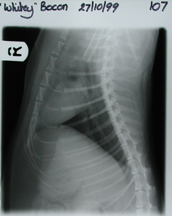

Radiography

This was an important adjunct to the intensive care nursing. Radiography was used to evaluate the extent of the injuries. See radiographs 1 to 9. This revealed the injuries described in the clinical history. The results from the radiographs showed that the cat had suffered right lung collapse, which was relevant information for subsequent intensive care. This meant that the cat should not be placed in left lateral recumbency, because the weight of the upper lung and heart always compromises the lower lung - so the good lung should never be placed under a dysfunctional one. This appeared to have quite a marked effect when the cat moved itself into left lateral recumbency, and dyspnoea increased within 2 to 3 minutes.

The cat responded well to the initial shock therapy but severe dyspnoea was a problem for 2 days, necessating oxygen therapy. Thereafter, although still dyspnoeic there was some improvement and oxygen therapy was no longer needed. On Day 4 the breathing became audibly wheezy, was treated, and seemed to resolve by Day 6. The cat's thorax was radio-graphed on the first, second and third day and each day unfortunately showed more haemorrhage. By Day 4, the breathing became audibly noisy. After treatment the breathing improved and by Day 8 appeared normal. Radiography on the first day showed that the bladder was intact and the cat was able to urinate. The cat was comfortable with the dressings and generally very bright. On Day 9 it was declared fit for orthopaedic surgery and has been booked for repair of the left hind and assessment of the right, after radiography of the thorax showed confirmation of a diaphragmatic line and clearing of the lungs. The radiographs/photos of the radiographs are arranged in chronological order.